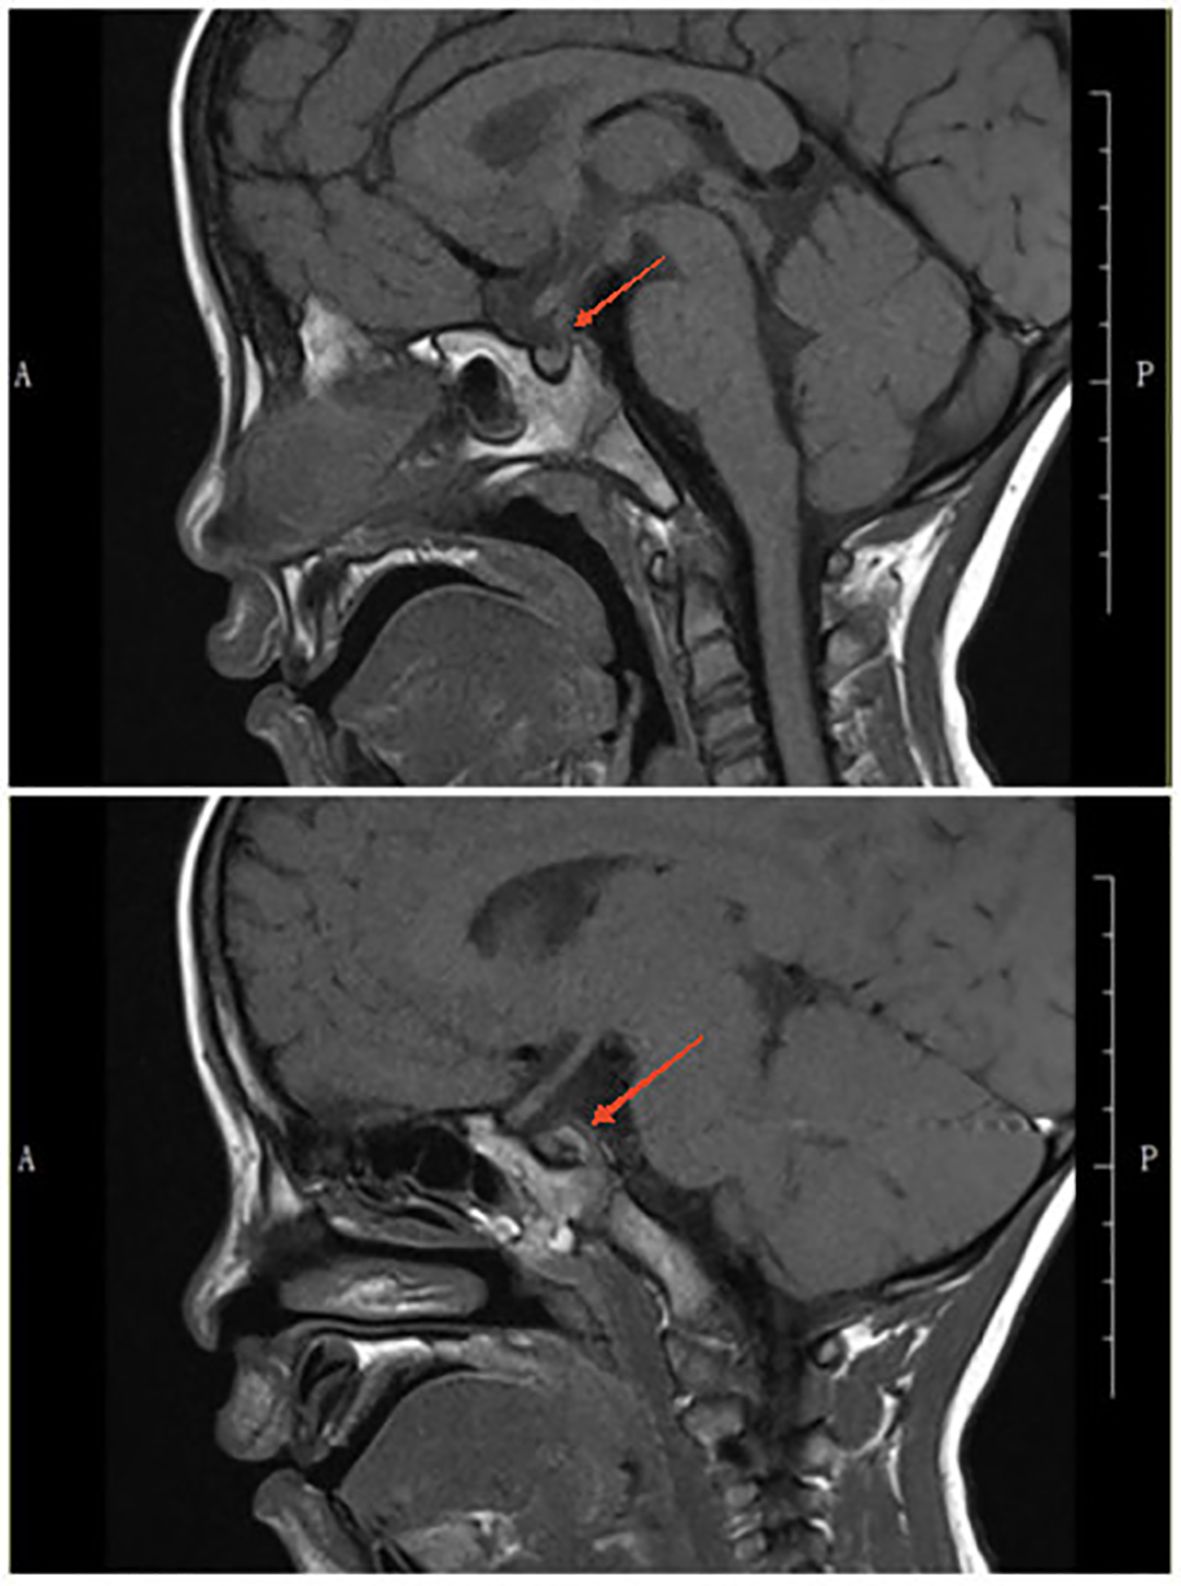

Rationale: SARS-CoV-2 infection can directly and indirectly affect the nervous system, including the hypothalamus and pituitary, and potentially cause IgG4-related hypophysitis. Patient concerns: A 4-year-old Chinese boy presented with arginine vasopressin deficiency (AVP-D, previously called 'central diabetes insipidus') and significant growth retardation. MRI indicated thickening of the pituitary stalk and alterations in the posterior pituitary. Diagnosis: The boy experienced polydipsia, polyuria, and enuresis 4 months after infection by SARS-CoV-2 and 2 months prior to presentation in June 2023. The diagnosis was IgG4-related hypophysitis, AVP-D, and growth hormone deficiency. Treatment with glucocorticoids and desmopressin led to significant resolution of symptoms and normalization of pituitary morphology. However, a second SARS-CoV-2 infection was followed by recurrence of polydipsia, polyuria, and thickening of the pituitary stalk. This recurrence led to a final diagnosis of IgG4-related hypophysitis caused by SARS-CoV-2 infection. Interventions: Glucocorticoids and desmopressin alleviated the AVP-D. Growth hormone and a diet and exercise plan were recommended to manage his short stature. We plan to conduct a functional assessment of the gonadal axis after he is 6 years old. Outcomes: After 18 months, the polydipsia and polyuria were controlled, and an MRI showed significant thinning of the pituitary stalk. This is the first reported case of lgG4-related hypophysitis in a Chinese boy infected with SARS-CoV-2. Lessons: We successfully controlled clinical symptoms, but further follow-up observations are needed to assess recovery. Although the role of SARS-CoV-2 infection in this patient's condition is only suggestive, other reports have described a relationship between SARS-CoV-2 infection and lgG4-related hypophysitis.